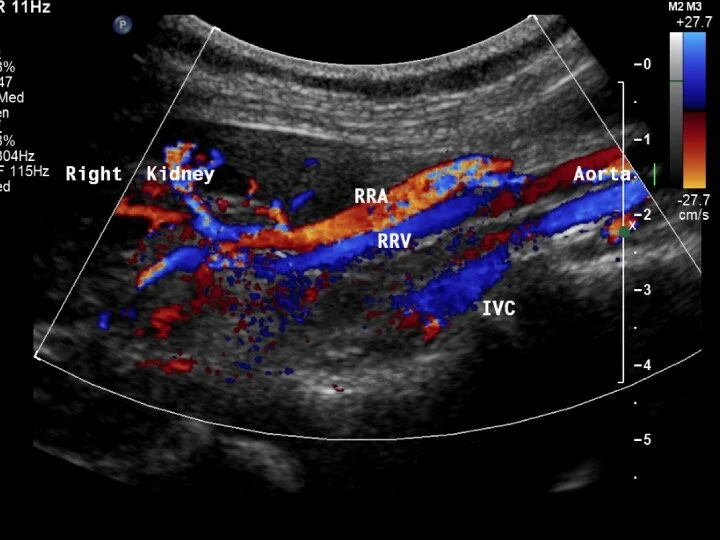

Duplex Ultrasound